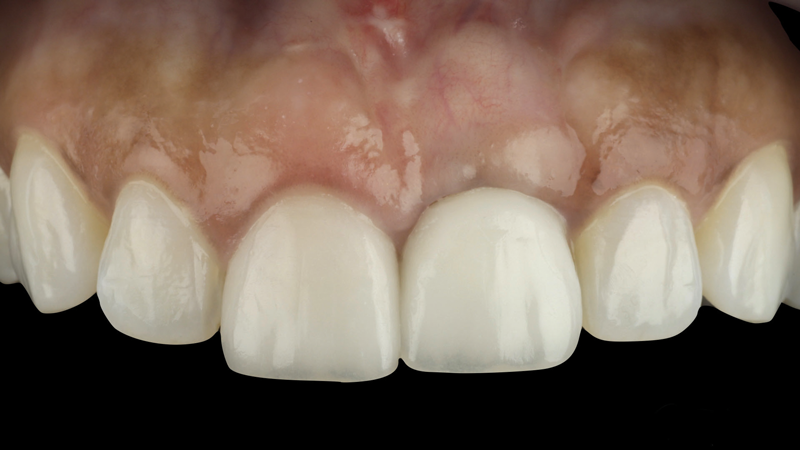

(21.) Eight-month postoperative frontal and occlusal views of the final restorations demonstrating continued stability of the gingival margin and volume.

Figure 21

(22.) Eight-month postoperative frontal and occlusal views of the final restorations demonstrating continued stability of the gingival margin and volume.

Figure 22